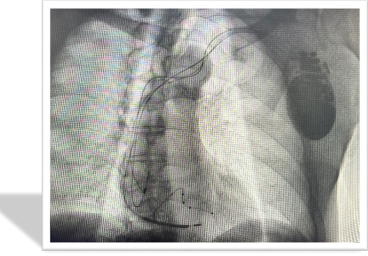

入院后,完善心脏彩超等一系列检查,明确诊断为急性心力衰竭(全心)、心功能Ⅲ级、扩张型心肌病、二尖瓣关闭不全、三尖瓣关闭不全、高血压病3级(极高危)、锁骨下动脉斑块儿。

业务范围:在心衰的非药物治疗方面经验丰富:针对难治性心力衰竭诊治开展了三腔起搏器(CRT/D)植入术;三腔起搏器程控和随访(起搏器参数调整)技术居领先水平,对植入ICD和CRT/D的患者进行参数调整和超声优化,减少放电次数,有效治疗顽固性心衰。床旁血滤治疗心衰也有丰富的临床经验;以体外反搏治疗为中心,率先在省内开展心力衰竭康复治疗,为慢性心力衰竭患者制定个体化康复治疗计划,取得良好效果。

学科特色:有专业的心衰治疗团队,设置有心衰门诊及心衰病房,床旁心电、血氧监测、医院配备快速血气分析、BNP、NT-proBNP、床旁彩超、床旁胸片,IABP、BiPAP呼吸机、床旁血滤等,为心衰的诊治提供了设备保障;

在心衰诊治中为患者提供优质的诊疗质量,包括1。明确心衰病因;2。遵循指南的药物规范治疗;3。心衰患者器械治疗,如心脏再同步化(CRT)、无创及有创呼吸机辅助呼吸、主动脉内球囊反搏(IABP)、体外膜肺氧合(ECMO)等。